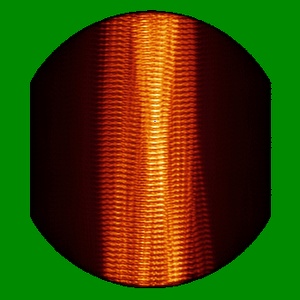

Helical reconstruction

2.68 Å

Straight filament from primary age-related tauopathy brain

Sample: Sarkosyl-insoluble fractions from primary age-related tauopathy brain

Fitted models: 7nrs